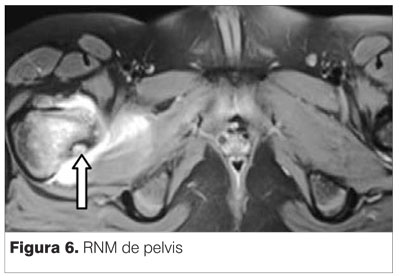

RNM informa asimetría en T2. Se observa claramente la lesión tumoral apoyada sobre la cortical posterior del cuello de fémur derecho (figuras 6, 7 y 8).